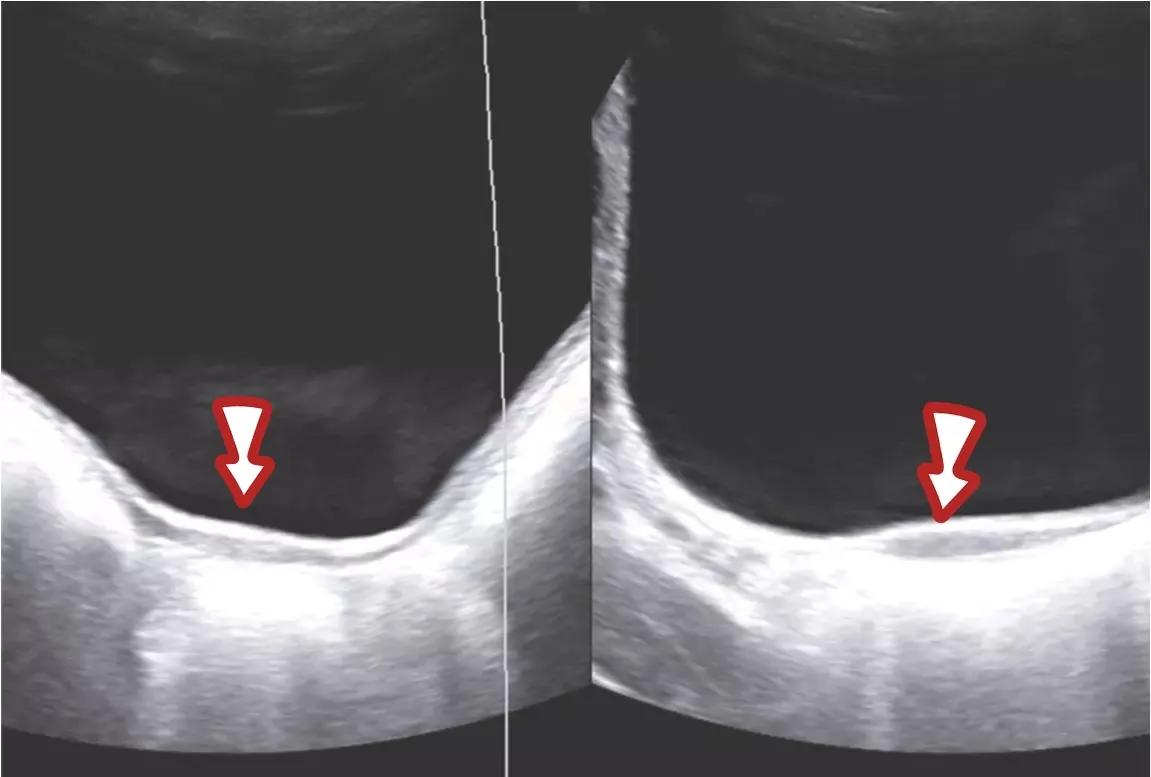

医生给开了个彩超,结果发现,小可两侧的卵巢都是正常的,但找来找去却看不见子宫,经由几个医生会诊,才发现一点点类似子宫的痕迹,一条小小的结构。

膀胱后方条索样的子宫结构

最终,大家认为小可属于始基子宫,没有内膜,所以没有月经。